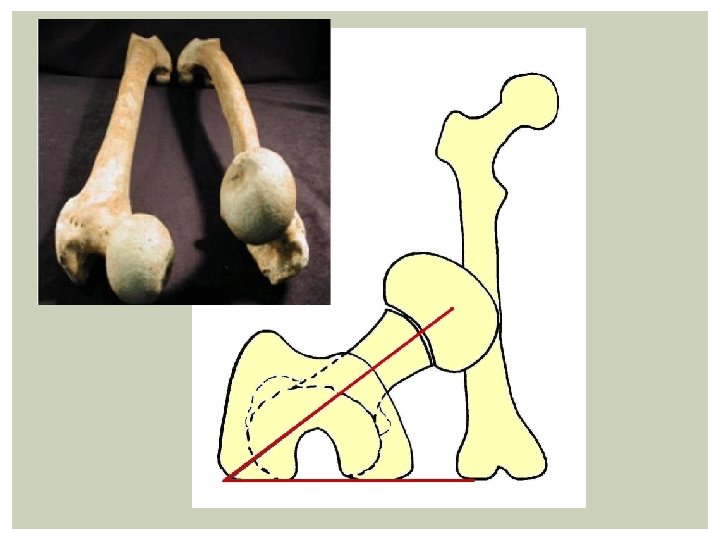

IN-TOEING GAIT Clinical assessment: Check symmetry Femoral anteversion/Medial tibial torsion/Metatarsus adducutus Natural progression: Femoral anteversion; normally self limiting by 8 years

FEMORAL ANTETORSION